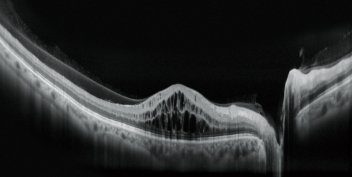

HD wide area OCT

The maximum 16.5 x 12 mm area scan available with the Mirante allows wide area diagnosis including the macula and optic disc in a single shot. The ultra fine mode and tracing HD plus functions provide high quality images for detailed observation from vitreous to choroid.

Macula Line 16.5mm / 2048 A Scans